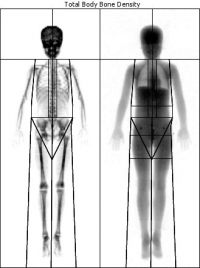

Umożliwia ocenę gęstości tkanki kostnej oraz składu ciała z wyznaczeniem masy tkanki tłuszczowej i mięśniowej u dzieci i młodzieży:

Analizie poddana zostaje wysokość ciała badanego dziecka względem normy dla zdrowych rówieśników.

Dysponujemy dużym, światowej klasy, stacjonarnym aparatem LUNAR PRODYGY PRIMO z wiarygodną referencyjną bazą danych.

Aparat Lunar Prodigy Primo posiada nowoczesne oprogramowanie do precyzyjnej diagnostyki dzieci i młodzieży.